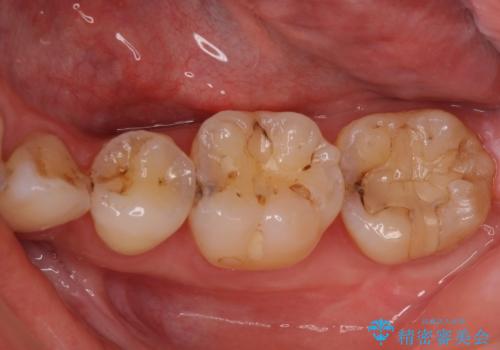

- 下の奥歯に虫歯ができてしまったとのことで来院された患者様です。

他にも気になる歯はありましたが、急を要する1歯のみをセラミックインレーにて修復治療を行うこととしました。

奥歯において、隣の歯と接触する部分に虫歯が及んでしまった場合、その場で充填を行う処置(コンポジットレジン修復)ですと、充填の縁に大きなギャップが生じてしまう可能性が高く、2次的な虫歯を引き起こすことになります。

また、処置した歯の後方にある歯は保険診療で使用するレジンインレーが装着されていますが、縁に虫歯が出来はじめていることが分かります。